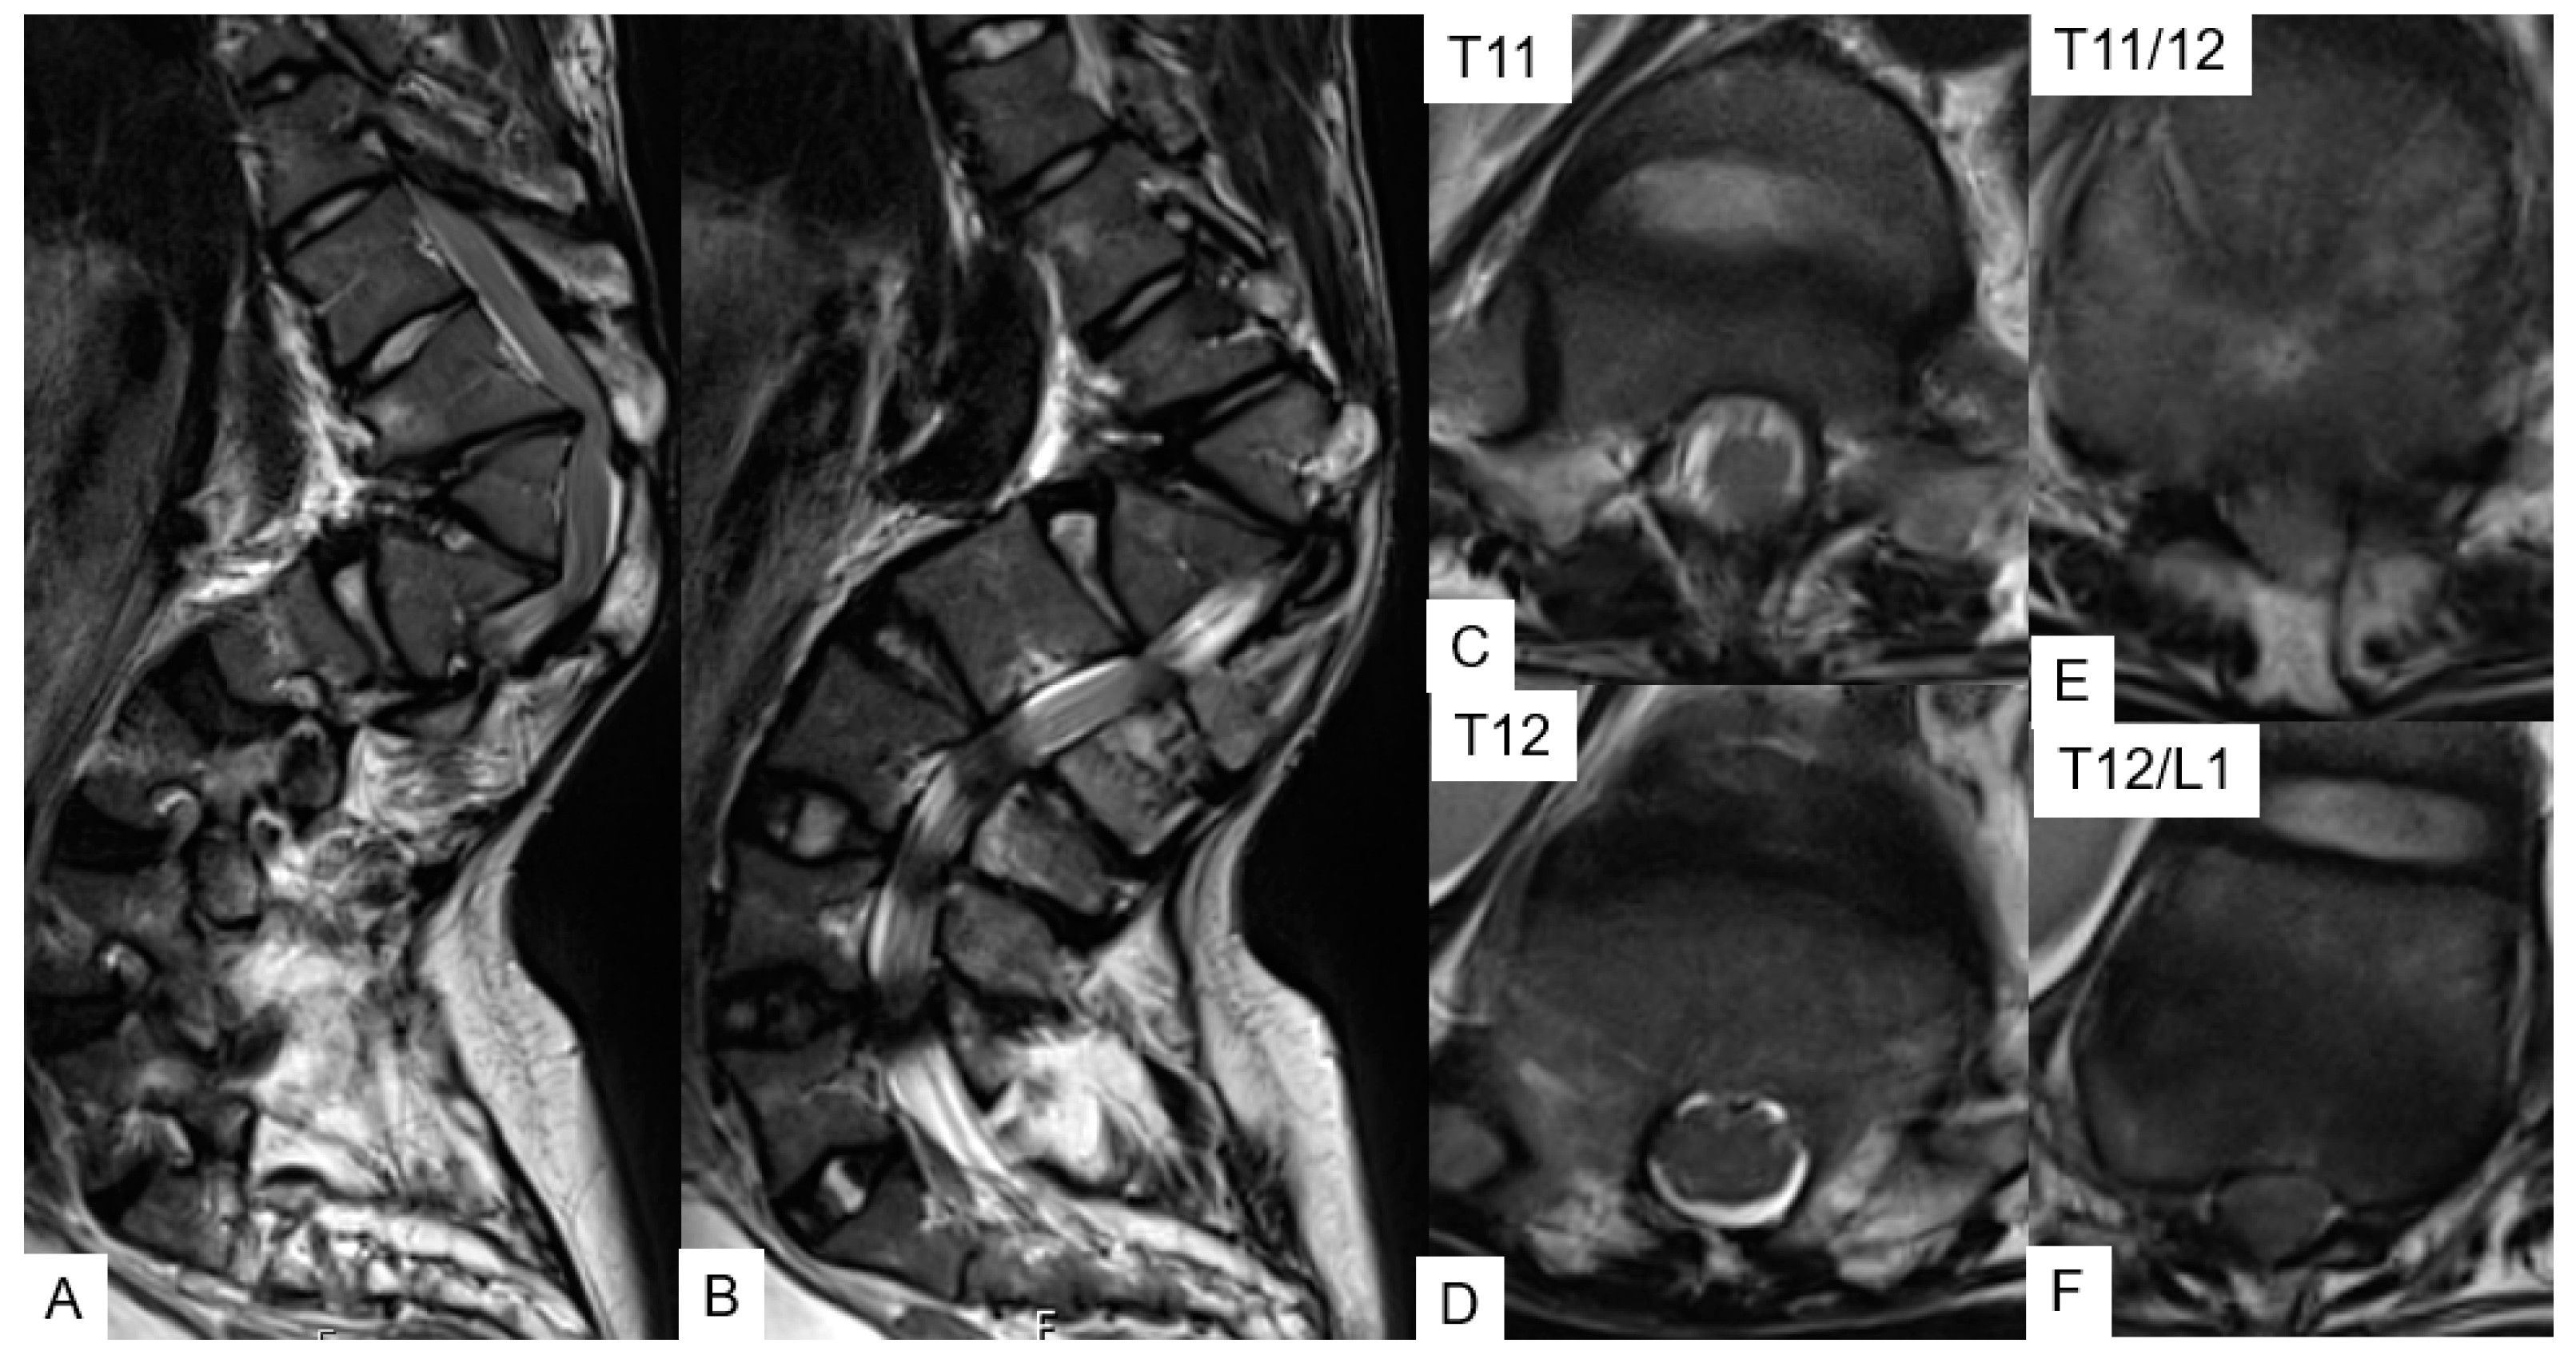

3.1.3. Preoperative Imaging

3.1.4. Surgery